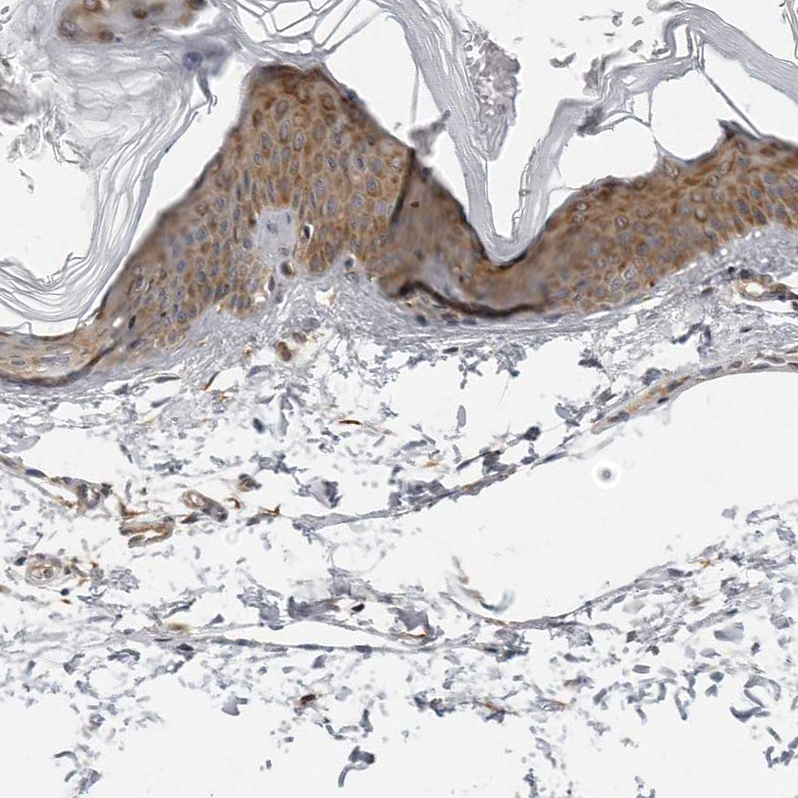

Immunohistochemical staining of human skin shows moderate to strong cytoplasmic positivity in squamous epithelial cells.